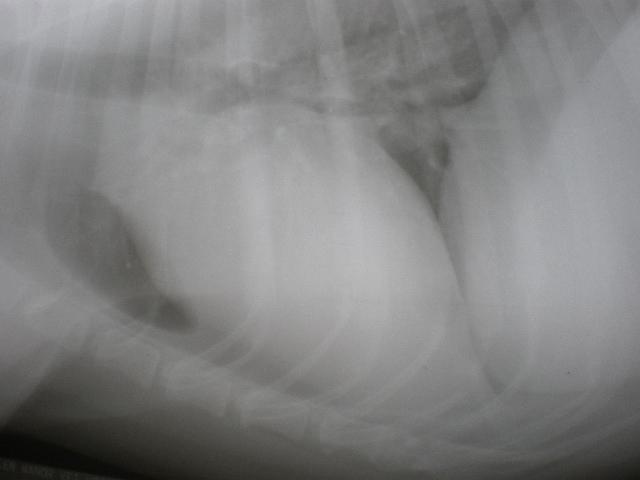

An 11-year-old MN Labrador retriever was prestented for excercise intolerance, lethargy, depression, vomiting and diarrhea. The physical exam was unremarkable other than a grade 2 left sided heart mumur at the heart base and irregular heart beat with pulse deficits. CBC, CHEM, UA, and acth stim were all normal.